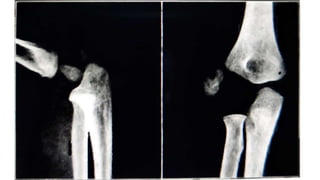

• Largest of pressure epiphysis – lower femoral epiphysis

• Serious injury of lower femur epiphysis is hyper extension type with

forward displacement of epiphysis

• Posterior corner of metaphysis may injur popliteal vessels

• Reduction is achieved by traction on semibent knee , pushing the

proximal fragment forward and then flexing the knee

• Reduction is most stable in 90° knee flexion

• Total period of immobilisation 3 weeks

• Largest ofpressure epiphysis – lower femoral epiphysis • Serious injury of lower femur epiphysis is hyper extension type with forward displacement of epiphysis • Posterior corner of metaphysis may injur popliteal vessels • Reduction is achieved by traction on semibent knee , pushing the proximal fragment forward and then flexing the knee • Reduction is most stable in 90° knee flexion • Total period of immobilisation 3 weeks